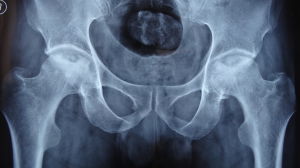

股骨頭壞死股骨頭壞死是股骨頭血供中斷或受損,引起骨細胞及骨髓成分死亡及隨後的修復,繼而導致股骨頭結構改變、股骨頭塌陷、關節功能障礙的疾病。ONFH可分為創傷性和非創傷性兩大類,前者主要是由股骨頸骨折、髖關節脫位等髖部外傷引起,後者在我國的主要原因為皮質類固醇的套用及酗酒

股骨頭壞死亦稱股骨頭無菌性壞死和股骨頭缺血性壞死,它是骨傷科臨床常 見而又難治的慢性疾病之一。股骨頭壞死是由於髖部外傷,長期套用激素類藥物,酒精中毒等原因,引起股骨頭血液供應障礙,股骨頭骨組織不能得到正常的營養,使股骨頭組織中的骨細胞,骨髓造血細胞,脂肪細胞發生壞死。由於壞死的 骨組織脆弱,加之髖關節需要負重,日久就會發生股骨頭塌陷,影響全部髖關節。本病有“輕則致殘,重則致癱”的說法

股骨頭壞死可發生於任何年齡但以31-60歲最多,無性別差異,開始多表現為髖關節或其周圍關節的隱痛、鈍痛,活動後加重,進一步發展可導致髖關節的功能障礙,股骨頭壞死嚴重影響患者的生活質量和勞動能力,若治療不及時,還可導致終身殘疾。